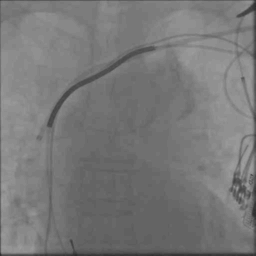

病例六

● 男,43岁,扩张性心肌病

● 术中见靶静脉狭窄,电极送入困难,采用球囊扩张、鞘中鞘技术送入电极